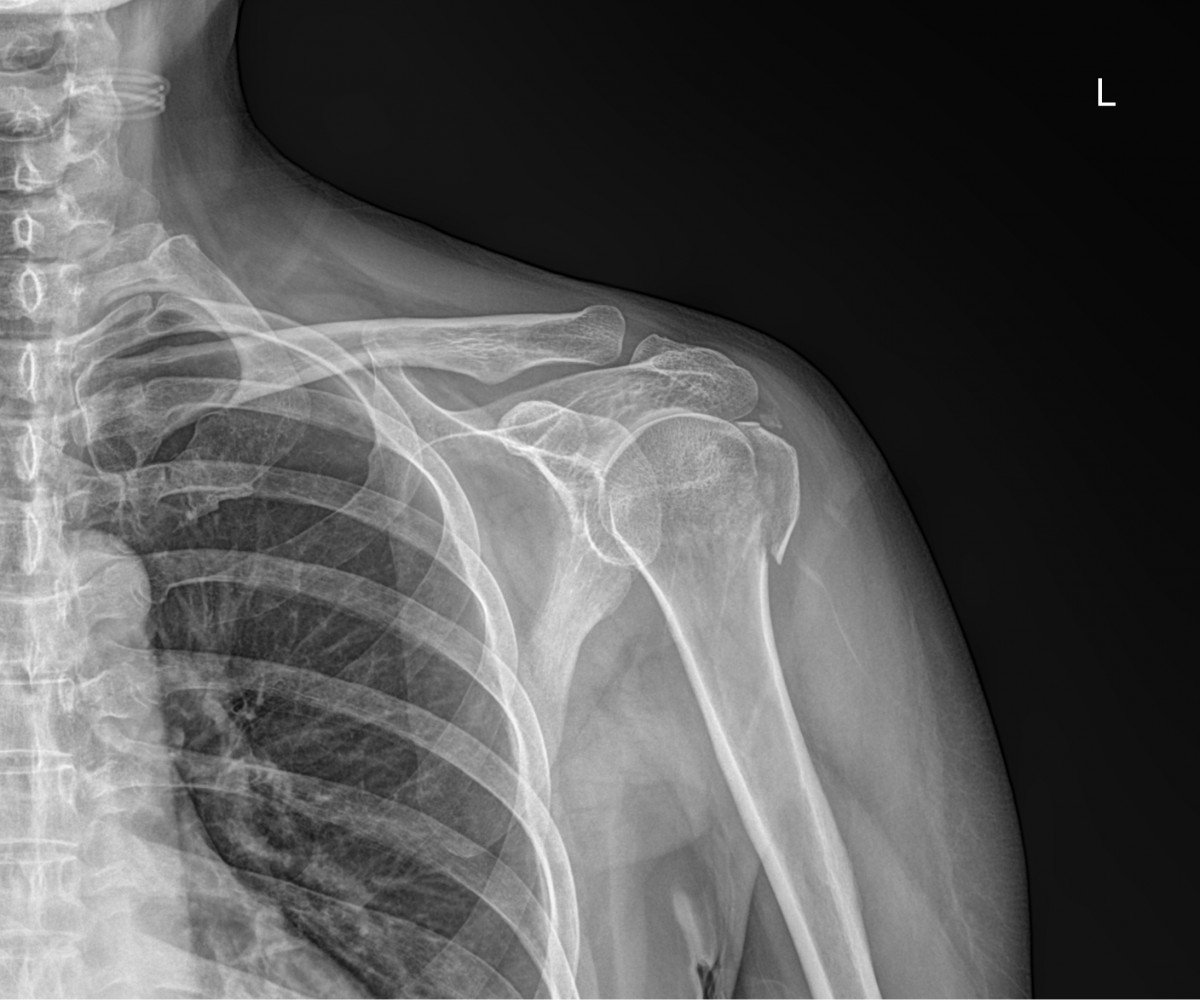

이재상원장님 어깨 골절 수술 고현O 환자

작성자 최고관리자 댓글 0건 조회 825회 작성일 25-09-16 14:48

dae765e4d9ac96aee867c9d6292d8784_1758001713_8375.jpg

dae765e4d9ac96aee867c9d6292d8784_1758001726_8396.jpg